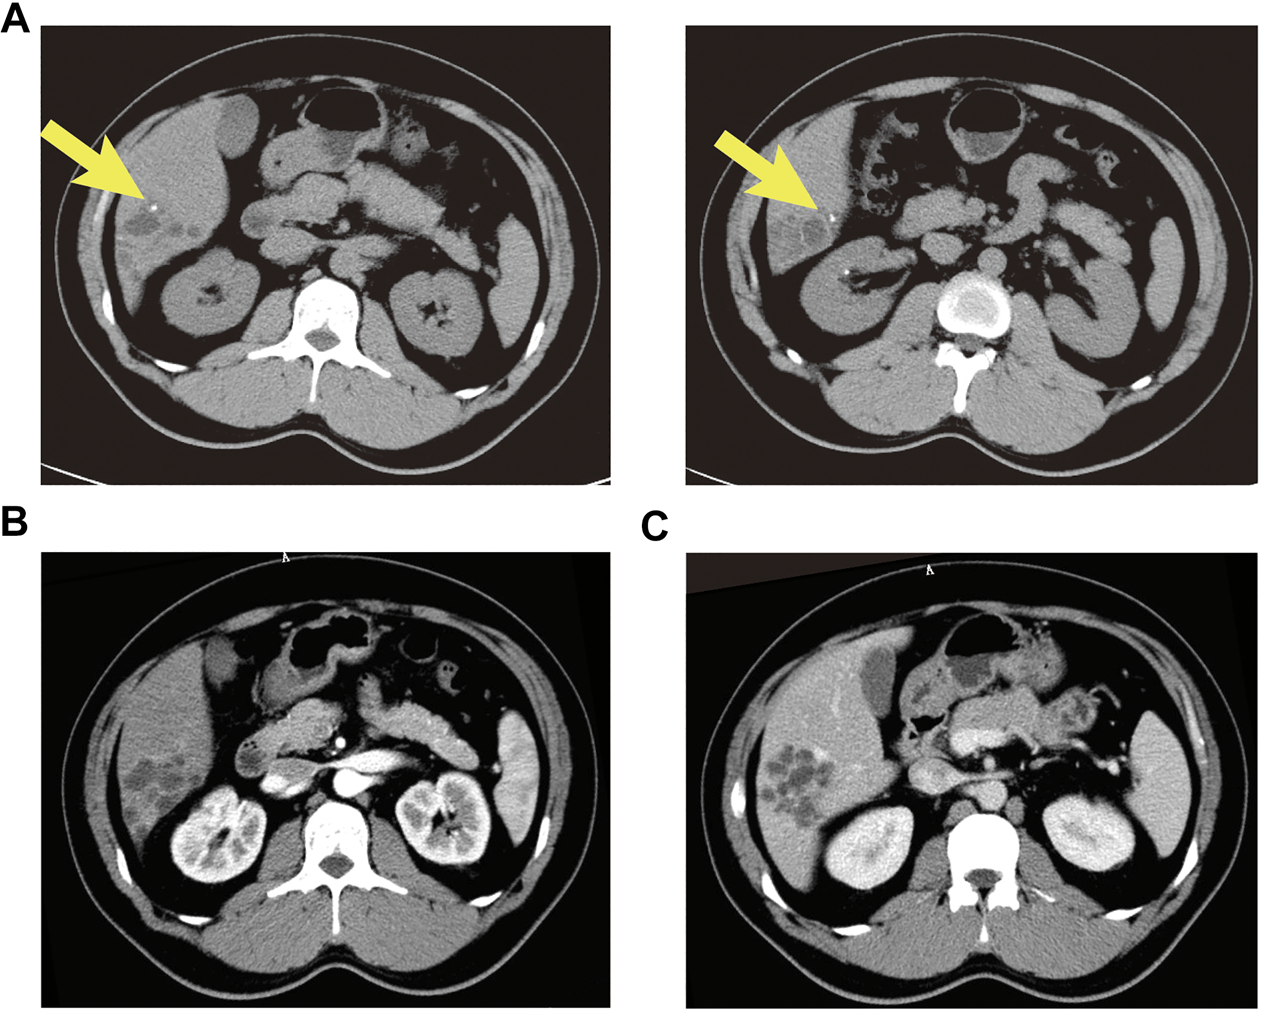

FIGURE 1

Abdominal contrast enhanced CT showed an intrahepatic multicystic mass in the segment VI of the liver. (A) Calcification was observed in dilated ducts (plain phase arrow); (B) The enhancement of the septa and peripheral wall within the cystic lesion (arterial phase); (C) The lesion showed a low-density honeycomb-like appearance (venous phase).

A 37-year old male patient was found to have a multicystic mass with the size 7.7*5.6 cm in the right hepatic lobe incidentally on abdominal ultrasonography. Then he was admitted to our hospital for mild abdominal distention after eating. Neither other significant clinical symptoms nor positive signs were found after further physical examination. Further examinations including liver function、tumor markers and abdominal contrast-enhanced computed tomography (CT) scan were performed. The laboratory results were as follows: alanine transaminase (ALT), 67U/L (normal: 9–40 U/L); carbohydrate antigen 19–9 (CA19–9), 65 U/mL (normal: 0–39 U/mL); other liver function and tumor markers were all in normal range. Abdominal CT revealed a multilocular cystic lesion in the segment VI of liver (Figure 1C). Interestingly, small calcification was found on precontrast CT (Figure 1A) and the septa and peripheral wall within the cystic lesion showed mild enhancement on postcontrast (Figure 1B). Based on these imaging results, we suspected that the lesion could be mucinous cystic neoplasm (MCN) or intraductal papillary neoplasm of the bile duct (IPNB) of the liver before operation. Laparoscopic complete resection of the lesion was performed (Figure 2). Intraoperative findings showed a lesion was grey-white lesion with multicystic surface. No enlarged lymph nodes were found during the operation. The cut surface of the resected specimen has many dilated ductal structures and hepatic parenchyma between these ducts, while bile-like material was observed within some ducts. Intraoperative frozen histopathological examination suggested preliminary diagnosis of biliary cystadenoma. Histopathological findings of formalin fixed paraffin embedded tissue on revealed periductal glands surrounded by connective tissue containing smooth muscle and small blood vessels but no ovarian-like stroma (Figure 3). Immunohistochemistry showed CK19 positivity of the dilated ducts epithelium and the small vessels were positive for CD30. Final histopathological diagnosis confirmed a multicystic biliary hamartoma (MCBH). After the surgery serum CA19–9 level dropped to normal range (28 U/mL) and there were no signs of recurrence 6 months after surgery.